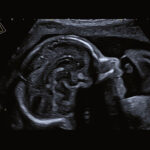

Specijalna premium kategorija za RTG, interne i gyn-por odjele. Lako se možete odmarati uz snažne performanse Aplia i600 na koje se možete osloniti u širokom rasponu kliničkih zadataka. U kombinaciji s nizom jednostavnih alata za naprednu dijagnostiku i precizan intervencijski rad, Aplio i600 osigurava dijagnostičku sigurnost i izvrsnu produktivnost.